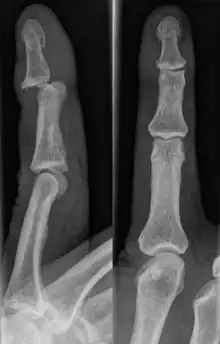

Dislocations can be categorised based on location and type. The finger can be split into three bones and two joints in an alternating order. From the fingertip to the knuckle, these are as follows; distal phalanx, distal inter-phalangeal (DIP) joint, middle phalanx, proximal inter-phalangeal (PIP) joint, and proximal phalanx. DIP dislocations are much less common than PIP dislocations,[2] due to the "stability provided by strong collateral ligaments, palmar plates, and tendinous insertions, as well as the short lever arm of the distal phalanx".[7] Dislocations can be categorised based on the direction that the fingertip moves in relation to the knuckle, be it in the direction of the palm (volar dislocation), or the direction of the back of the hand (dorsal dislocation). Of the two, dorsal dislocations are more common.[3] If reduction has been attempted, an x-ray of the dislocation should appear concentric if successful.[2] However, if there is a fracture present, there will be a misalignment of the joint, which will be evident from the radiograph.[2] Bach suggests a referral to a hand surgeon if a misalignment is present.[2]

Fractures are instances where the bone's structural integrity has been compromised. This is indicated by midshaft pain, as well as visual midshaft angulation or rotation.[3] As with any skeletal injury, an x-ray can be conducted to verify the presence of a fracture.[1] The distal phalanx is especially vulnerable to avulsion fractures, where a fragment of bone is ripped off when the tendon separates from the phalanx.[1] Avulsion fractures are especially common following a first time dislocation.[1] These are especially concerning, as it may indicate a complete tear of the extensor digitorum tendon. If left untreated, this may lead to permanent DIP extensor lag (inability to fully straighten the finger).[8]

DIP Dislocation

PIP Dislocation